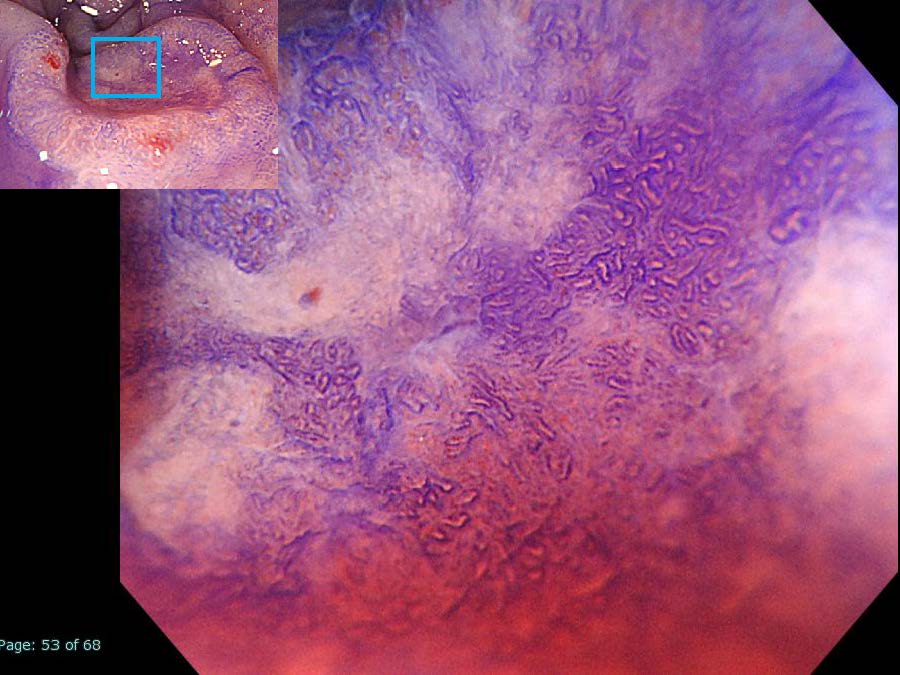

消化管Mapping~大腸~ 2021.10.27

消化器センター 消化器内科

消化管Mapping

消化管Mapping~大腸~

内視鏡検査・治療